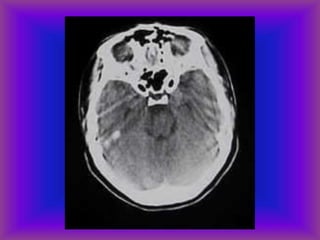

Acute subarachnoid hemorrhage

(and intraventricular)

Cerebral Hemorrhage